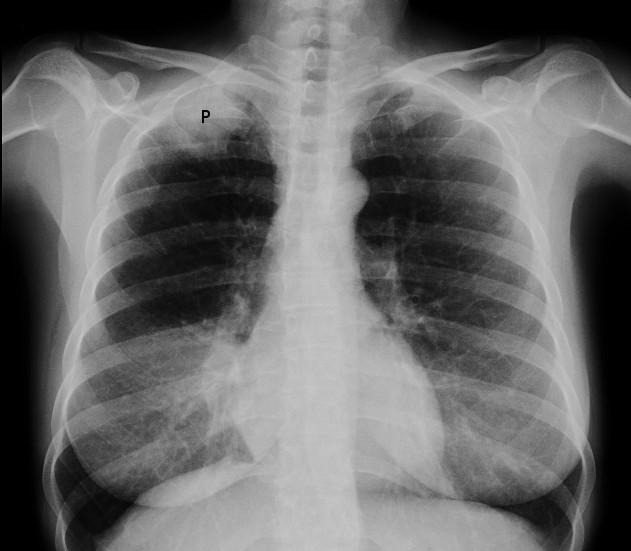

X-ray image of Pancoast tumour

By Jmarchn, CC BY-SA 3.0, via Wikimedia Commons